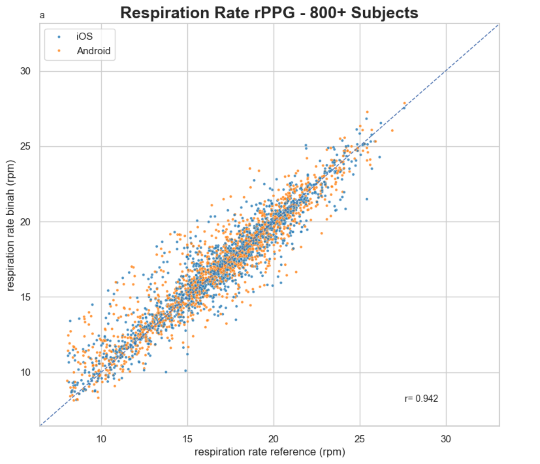

Briah.ai’s revolutionary contactless (rPPG) technology delivers precise heart rate variability (HRV) measurements, offering deep insights into autonomic nervous system function and overall cardiovascular health. Our AI-driven solution ensures highly accurate RR interval assessments, validated against reference devices across iOS and Android platforms.

Our technology meets high accuracy standards and has been validated through extensive research and testing.